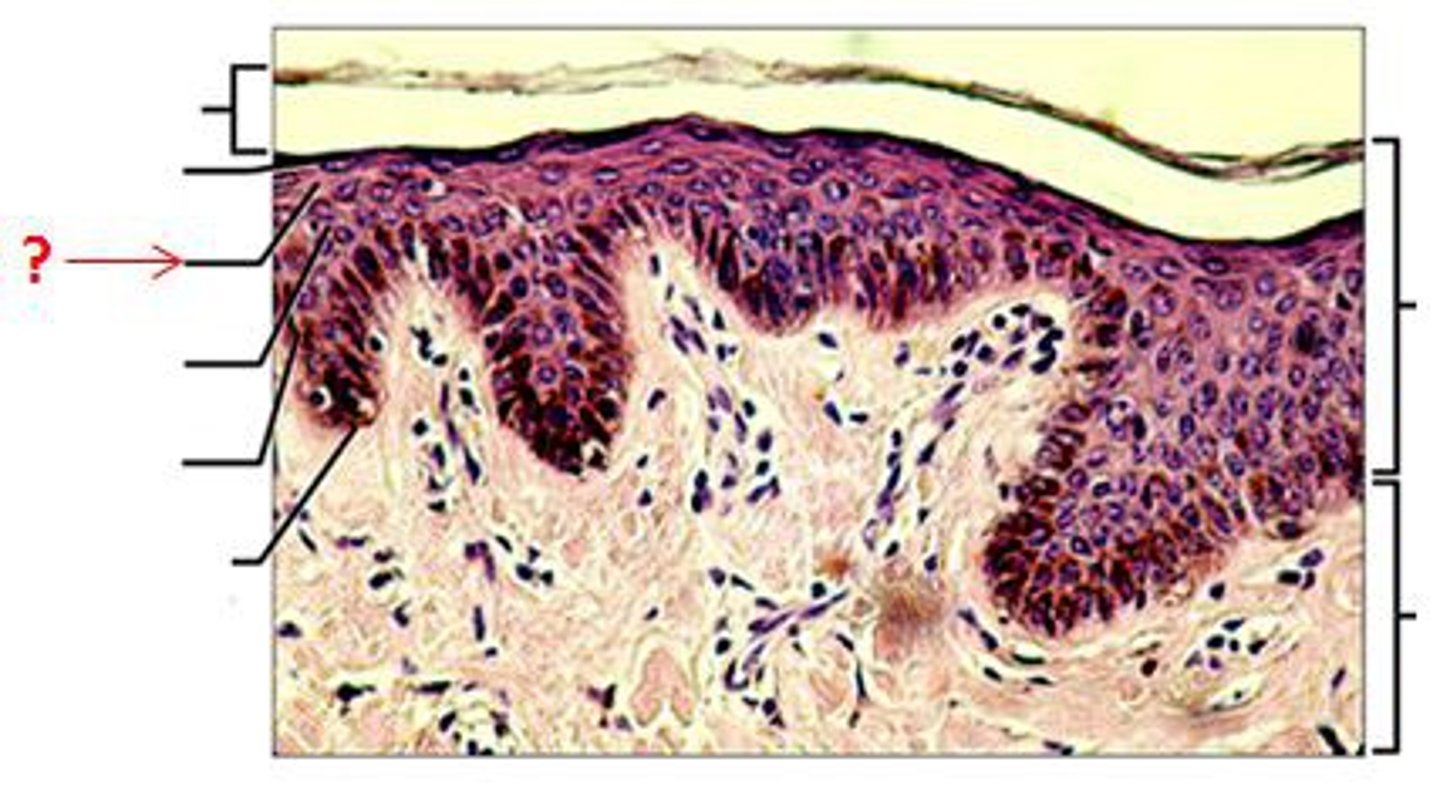

Epidermis

Outer layer of skin

stratum corneum

outermost layer of epidermis

stratum lucidum

Clear, transparent layer of the epidermis under the stratum corneum.

stratum granulosum

a layer of the epidermis that marks the transition between the deeper, metabolically active strata and the dead cells of the more superficial strata

stratum spinosum

stratum basale

the deepest layer of the epidermis consisting of stem cells capable of undergoing cell division to form new cells

Dermis

Inner layer of skin

papillary layer

outer layer of the dermis, directly beneath the epidermis; made of loose connective tissue

reticular layer

The deeper layer of the dermis that supplies the skin with oxygen and nutrients; made of dense irregular connective tissue

dermal papillae

a fingerlike projection of the dermis that may contain blood capillaries or Meissner corpuscles (of touch)